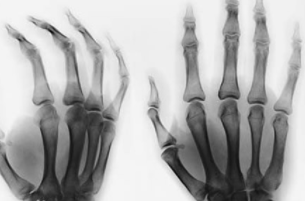

- 编号

TF16010039 姓名:王先生 性别:男 年龄:41岁

- 病情

痛风 ①晚期 ②并发症 病史:12年+

- 治疗

治疗后手指关节、脚趾关节痛风石完全清除,血尿酸降至正常水平,手脚各关节痛感消失,关节活动恢复到正常状态。 ??